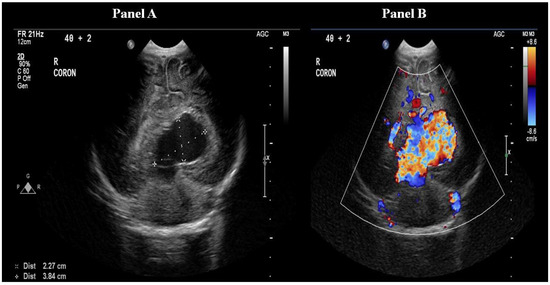

Following the stabilisation of the patient, a cranial ultrasound was performed, which showed a large anechoic structure mainly to the left of the midline posteriorly, with marked internal vascularity and prominent flow in keeping with the vein of Galen aneurysmal malformation (VGAM). The dilated median prosencephalic vein measured 36 × 26 × 29 mm (Figure 2). Clinical examination at this stage revealed cranial bruit, which was missed on admission.

Figure 2.

Coronal head ultrasound demonstrating an anechoic structure measuring 36 × 26 × 29 mm, consistent with dilated median prosencephalic vein (Panel A), and ultrasound with Doppler demonstrating increased flow in the dilated prosencephalic vein (Panel B).